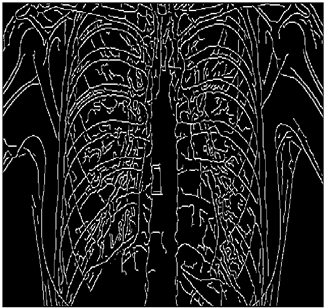

Table 14. Edge-detected image of “X-ray 5” after binarization for different noises.

NoiseCannyStandardSmooth

No noise Mathematics 10 02421 i156 Mathematics 10 02421 i157 Mathematics 10 02421 i158

G(0.001) Mathematics 10 02421 i159 Mathematics 10 02421 i160 Mathematics 10 02421 i161

G(0.002) Mathematics 10 02421 i162 Mathematics 10 02421 i163 Mathematics 10 02421 i164

G(0.003) Mathematics 10 02421 i165 Mathematics 10 02421 i166 Mathematics 10 02421 i167

I(0.25%) Mathematics 10 02421 i168 Mathematics 10 02421 i169 Mathematics 10 02421 i170

I(0.5%) Mathematics 10 02421 i171 Mathematics 10 02421 i172 Mathematics 10 02421 i173

I(1%) Mathematics 10 02421 i174 Mathematics 10 02421 i175 Mathematics 10 02421 i176

Table 14 shows the following:

• In all cases, the Canny edge detector detects more edge pixels than both fuzzy compositions.

• As the level of noise increases, all three methods become adversely affected by the noise, and still more edges are detected by Canny; however, most of the detected edges by Canny are misdetections due to the impact of noise. As is obvious from this table, the standard composition as well as the smooth composition somehow show equal performance in reducing noise density.

• However, in all cases, the PFOM value for the smooth composition is always greater than the PFOM value for the standard composition, according to Table 6.